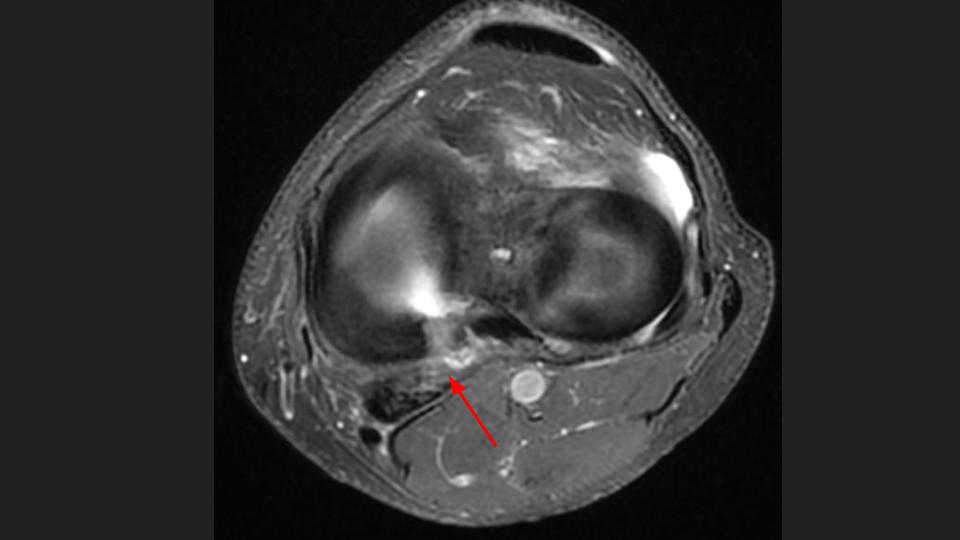

49M runner with pain since twisting injury during marathon 1 year ago

There is a radial tear / avulsion of the posterior horn medial meniscal root (red arrow), which is likely related to the running injury 1 year ago. There is stress related marrow edema, but it is not localized deep to the root anchor. There is 3mm (borderline) extrusion of the medial meniscal body (white arrow), but there is surprising preservation of the medial compartment articular cartilage. Meniscal root tear is known to predispose to medial compartment cartilage loss, which is often rapid. Hes obviously symptomatic and has stress related marrow edema, but why hasnt he developed medial compartment OA?

posterior horn of medial meniscus ( RID2776 )